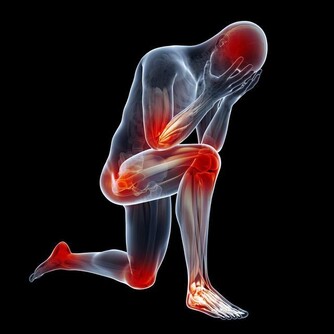

心氣虛病因:或勞累過度,或心情抑鬱而暗耗心陰,或受刺激而鬱鬱不歡,或步入中年氣虛,大病初癒氣已傷。

陽虛和陰虛特點如下:

陽虛,舌嫩胖而苔白、舌尖有潰瘍、長吁短嘆且自汗、心區憋悶透不過氣、心裡怯懦。

陰虛,舌瘦而苔躁紅、面紅燥熱而自汗、心區燥熱、煩悶易發火。